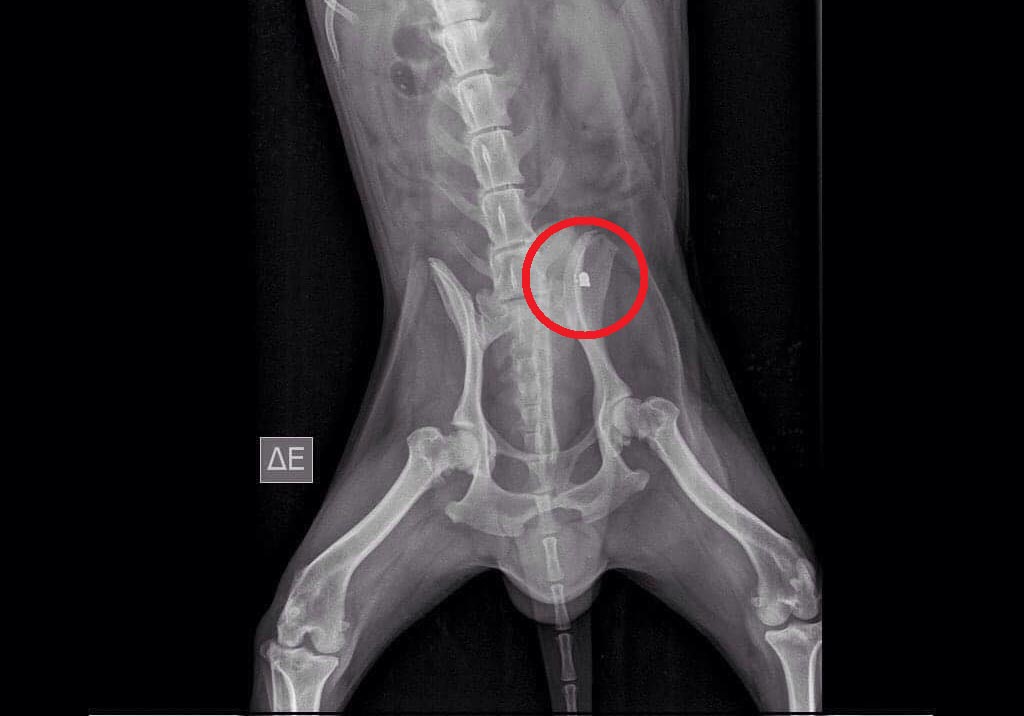

Στο κτηνιατρείο της Παναγιώτας Τσάγκου στα Λεχαινά νοσηλεύεται ο σκύλος ο οποίος εντοπίστηκε χθες στην περιοχή Συκιά κοντά στο λιμάνι στο Κατάκολο της Ηλείας. Το ζώο όπως εξήγησε στο www.zoosos.gr η Αργυρώ Χριστοδουλάκη το βρήκε να περπατάει εξαιρετικά περίεργα,  με μεγάλη δυσκολία κάπως λοξά και όπως φάνηκε τελικά από τις ακτινογραφίες είχε πυροβοληθεί με αεροβόλο στη λεκάνη.

KatakoloIliasPyrovolimenosAerovoloSkylosAktinografia 2Η ακτινογραφία έδειξε το σφαιρίδιο στη λεκάνη του ζώου.

Η κα Χριστοδουλάκη κατάφερε να το πιάσει μετά από πολλές προσπάθειες καθώς το ζώο ήταν εξαιρετικά φοβισμένο και το μετέφερε στο κτηνιατρείο. Η κα Τσάγκου εξήγησε στο www.zoosos.gr ότι τις επόμενες μέρες θα φανεί αν πρέπει να αφαιρεθεί το σφαιρίδιο ή όχι και αν η ζημιά που έχει κάνει στο ζώο, στη βάδιση του είναι αναστρέψιμη.